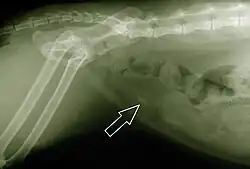

.jpg)

A leucemia felina, provocada por um vírus, é uma das doenças mais complexas que afeta os gatos. Diferentemente da versão humana da doença, é contagiosa, podendo ser transmitida de gato para gato por meio da saliva ou pelo contato com sangue contaminado. No entanto, não é transmitida aos seres humanos, tendo em vista que o agente causador somente sobrevive no organismo dos felinos.[125] A vacinação contra a leucemia confere proteção aos gatos em 95% dos casos. A castração reduz a possibilidade de contaminação, já que o animal tende a permanecer mais em casa e não ter contato com outros gatos.

A leucemia felina é uma doença desconhecida por muitos veterinários, que, ao não saber como tratá-la, recomendam o sacrifício do animal. Inicialmente, esta doença se manifesta pela perda parcial da defesa imunológica do gato portador. Porém, trata-se de uma doença degenerativa, cuja gravidade vai avançando ao mesmo tempo que reduz a expectativa de vida em alguns anos. Tratamentos podem abrandar os problemas, sobretudo se o gato viver em boas condições, uma vez que, devido à baixa imunidade, qualquer doença de menor gravidade pode ser altamente perigosa para o animal. Durante o estado crítico, o gato necessita de cuidados e boa alimentação, acompanhado por veterinários, e do uso do interferon. A leucemia felina "terminal" ocorre quando a doença atinge a medula óssea, anulando totalmente a produção de glóbulos brancos à sua defesa; quando esta ocorre, o animal começa a ter a sua saúde deteriorada rapidamente e passa a sofrer fortes dores, de modo que o sacrifício é a única solução.[172]